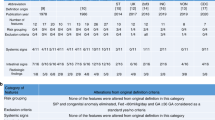

Five clusters of intestinal injury were identified: Cluster 1 deemed the “Low Mortality” cluster, Cluster 2 deemed the “Mature with Inflammation” cluster, Cluster 3 deemed the “Immature with High Mortality” cluster, Cluster 4 deemed the “Late Injury at Full Feeds” cluster, and Cluster 5 deemed the “Late Injury with High Rate of Intestinal Necrosis” cluster.